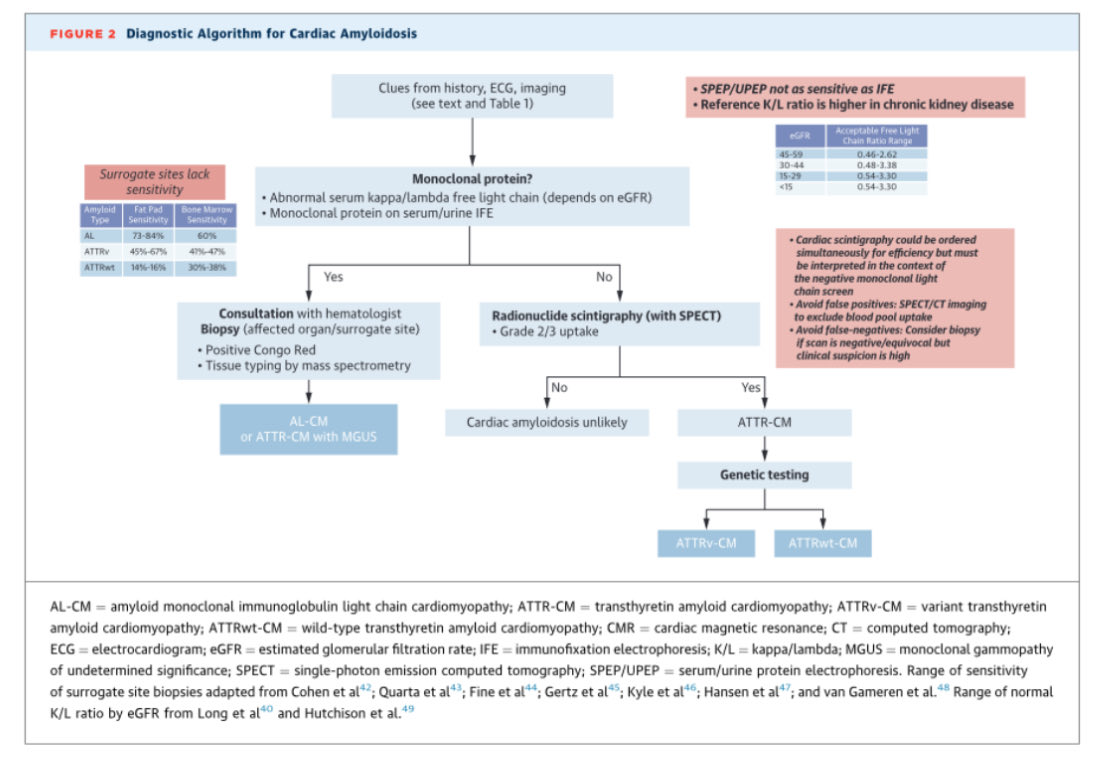

🔴 Transthyretin Cardiac Amyloidosis Evaluation and Management: 2025 ACC Concise Clinical Guidance @JACCJournals #Cardiology #CardioEd #Amyloidosis #FOAMed